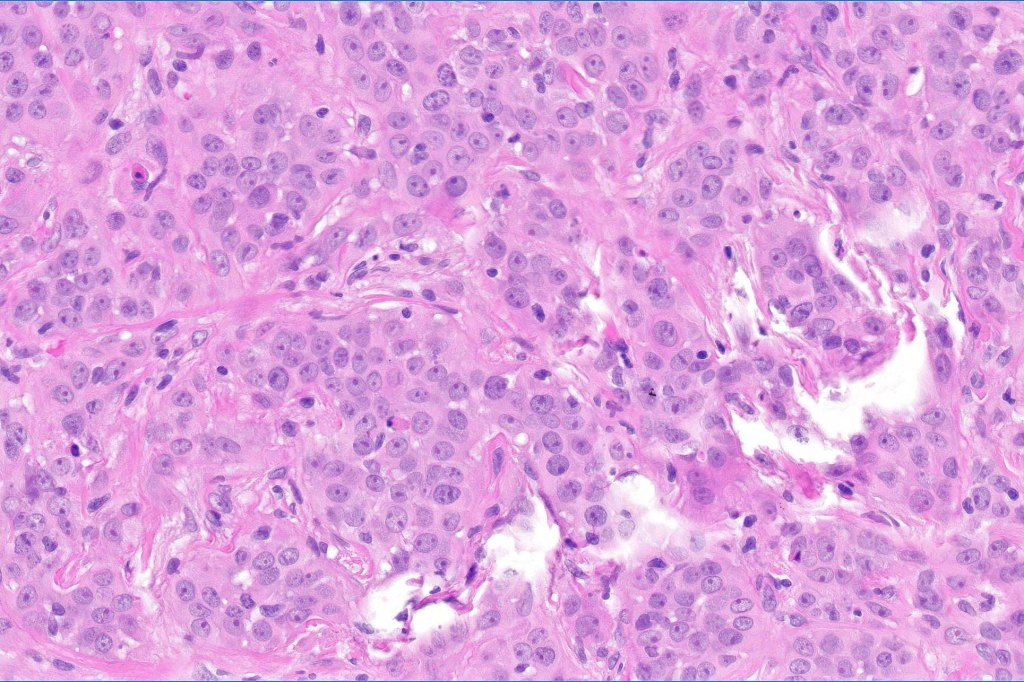

•Adenocarcinoma in deeper reaches

•Variable pleomorphism and mitotic activity

•Deep part may show both ducts and glands

•Often extends to the subcutaneous fat